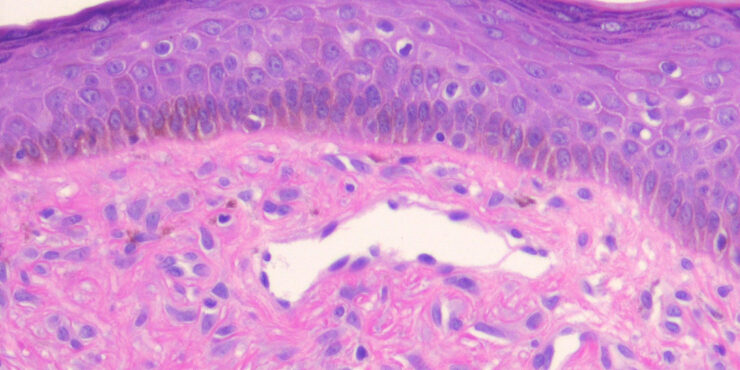

Read MoreFibrous papule (angiofibroma) = حطاطة تليفية =ليفوم وعائي OLYMPUS DIGITAL CAMERA OLYMPUS DIGITAL CAMERA FIBROUS PAPULE Currently, there is some disagreement as to whether fibrous papule represents a neoplastic process or a hamartoma.Fibrous papule (perifollicular fibroma) presents mainly as a solitary papule or as several dome-shaped, skin-colored, pigmented, or reddish lesions situated on the face, […]